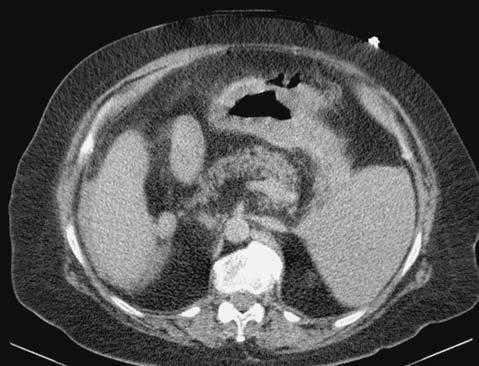

Se presenta una paciente de 66 años que acude a urgencias por disnea, falta de expulsión de gases y heces y dolor abdominal de 24-48 h de duración; además, náuseas y vómitos en posos de café. Presenta como antecedentes personales diabetes mellitus no dependiente de insulina, situs inversus totalis e intervenciones quirúrgicas previas de colecistectomía y apendicectomía. El estado general impresiona de gravedad: presión arterial, 140/58 mmHg; frecuencia cardíaca, 135 lat/min; temperatura axilar, 37,5 °C; SaO2 del 93,5%, y disminución del murmullo vesicular de base pulmonar derecha. Presenta defensa, peritonismo difuso y silencio abdominal. Los valores analíticos sanguíneos son: 30.700 leucocitos (el 93,2% neutrófilos); amilasemia, 367; glucosa, 354 mg/dl; dímero D de 1.343 ng/ml, y pH sanguíneo de 7.08; el resto, dentro de la normalidad. La tomografía computarizada muestra situs inversus totalis y pequeño neumoperitoneo que parece en continuidad con el aire del estómago (fig. 1).

Fig. 1. Tomografía computarizada sin contraste. Se muestra líquido libre periesplénico y pequeña imagen de neumoperitoneo cerca del estómago que indica perforación de esta víscera hueca. Obsérvese el situs inversus abdominus completo.